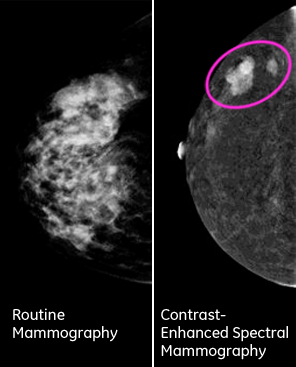

L'angiomammographie est une nouvelle technologie dont vient se doter le centre hospitalier d'Armentières, dans le Nord de la France.Le Senobright développé par General Electric Healthcare (application) permet de donner un diagnostic aussi précis que l'IRM mais avec plus d'info et avec moins d'irradiation qu'une mammographie